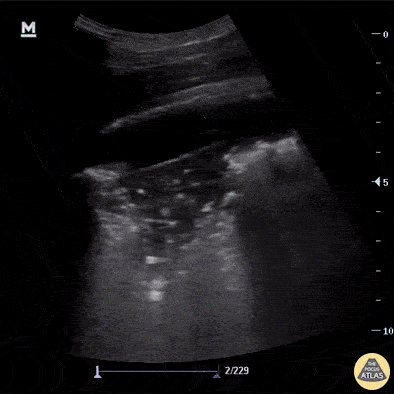

Pictured here are classic ultrasound findings for pneumonia including a shred sign, lung consolidation with dynamic air bronchograms and a small associated parapneumonic effusion. Note also adjacent B-lines. A shred sign represents the distinction between the consolidated lung and the aerated lung and is seen in this clip as the irregular “shredded” border just posterior to the consolidation. Aaron Inouye, PA-C, North Canyon Medical Center @PAintheED